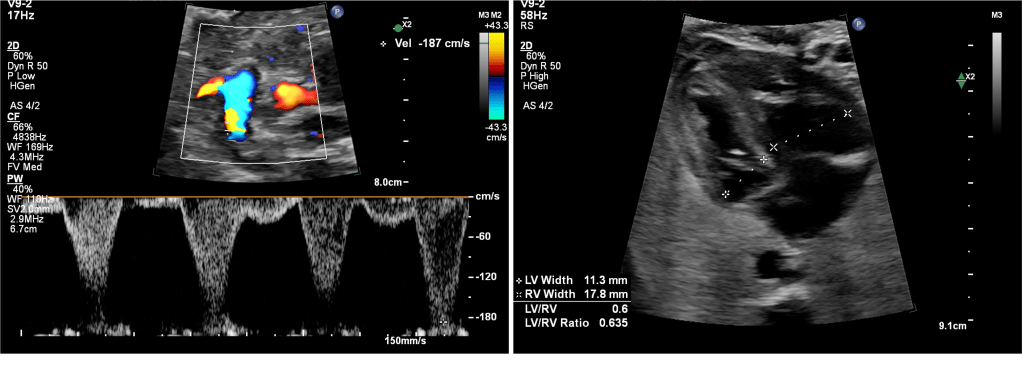

Detection relies on Doppler assessment of ductal flow and evaluation of the fetal right heart. Key elements include ductal peak systolic velocity (PSV), pulsatility, diastolic flow, and secondary RV changes.

4. Functional Severity Assessment

Severity is defined by functional consequences rather than velocity alone.

• Mild: Preserved pulsatility, forward systolic and diastolic flow, normal RV size and function.

• Moderate: Reduced pulsatility, shortened diastolic flow, mild RV hypertrophy or tricuspid regurgitation (TR).

• Severe: Minimal or absent diastolic flow, non‑pulsatile waveform, RV dilatation or dysfunction, moderate–severe TR.

Role of Myocardial Performance Index (MPI)

Right ventricular MPI (Tei index) provides an objective measure of global RV function. In the absence of robust gestation‑specific cutoffs, an MPI value above approximately 0.45 is considered suggestive of RV pressure overload and should upgrade severity classification.

5. Ductal Arch View: Practical Imaging Recommendations

• Use a longitudinal ductal arch view of the fetus.

• Ensure near‑parallel insonation.

• Avoid oblique sampling from the three‑vessel trachea view alone.

• Assess flow pattern, not velocity alone.